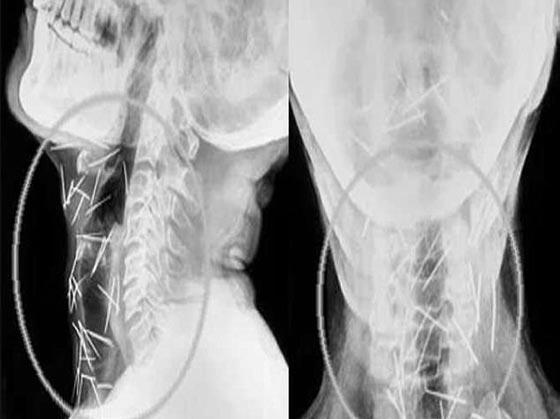

أما آخر حالة حيّرت الأطباء لدى عثورهم على عشرات الدبابيس المغروزة في مختلف أنحاء جسد رجل لا يعرف كيف وصلت هناك! واضطر الهندي بدريلال مينا، البالغ من العمر 56 عاماً، إلى زيارة ستة مستشفيات والخضوع لثلاث عمليات جراحية لاستخراج الدبابيس المغروزة في ذراعيه وقدميه وعنقه. ووفقاً لتقارير الأطباء، أزيل حتى الآن 91 دبوساً، وكان بعضها صدئاً جداً لوجوده هناك لأكثر من ستة أشهر.

ويقول الدكتور لاليت موهان باراشار، الذي أجرى العملية لمينا، "كان إخراجُ الدبابيس بأمان أمراً في غاية الصعوبة، حيث إن بعض الدبابيس كان موجوداً في القصبة الهوائية، والمريء، وحتى في الشريان السباتي الذي يحمل الأكسجين إلى الدماغ". لكن مينا يُصرّ على أنه لم يغرزها بنفسه، ويدعي أنه ليس لديه فكرة عن كيفية دخولها إلى جسده. وكان مينا في بداية الأمر، قد ذهب إلى مستشفى خاص وهو يشكو من آلامٍ في القدم ومن داء السكري؛ ولكن الأطباء وجدوا 75 دبوساً في أجزاء مختلفة من جسده، فيما وجد المعهد الآسيوي للعلوم الطبية في فريداباد (AIMS) - الذي تبنى حالة مينا- 75 دبوساً آخر. ويوضح المعهد أن المهمة الأكثر صعوبة هي "إزالة تلك الدبابيس التي اخترقت الأعصاب الحيوية والشرايين والأعضاء، مثل المريء والشريان السباتي الذي يزود الدم بالدماغ". وأذهل ازدياد عدد الدبابيس الأطباء، لا سيما وأن مينا يُصرُّ هو وأسرتُه على أنه لم يغرز نفسه بهذه الدبابيس، فيما أوصت سلطات المستشفيات بإجراء تقييم نفسي له بعد تعافيه.